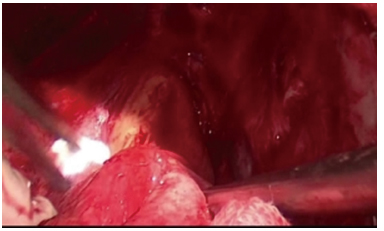

胸膜中皮腫や肺癌に対する胸膜外肺全摘術

Extrapleural pneumonectomy for pleural mesothelioma or lung cancer

胸膜中皮腫に対する胸膜切除剥皮術

Pleurectomy/Decortication (P/D) for pleural mesothelioma

▼私の胸膜外肺全摘術の手術写真1-9 (My EPP photo 1-9)

▼私の胸膜切除/剥皮術の手術写真 1-10 (My P/D photo 1-10)